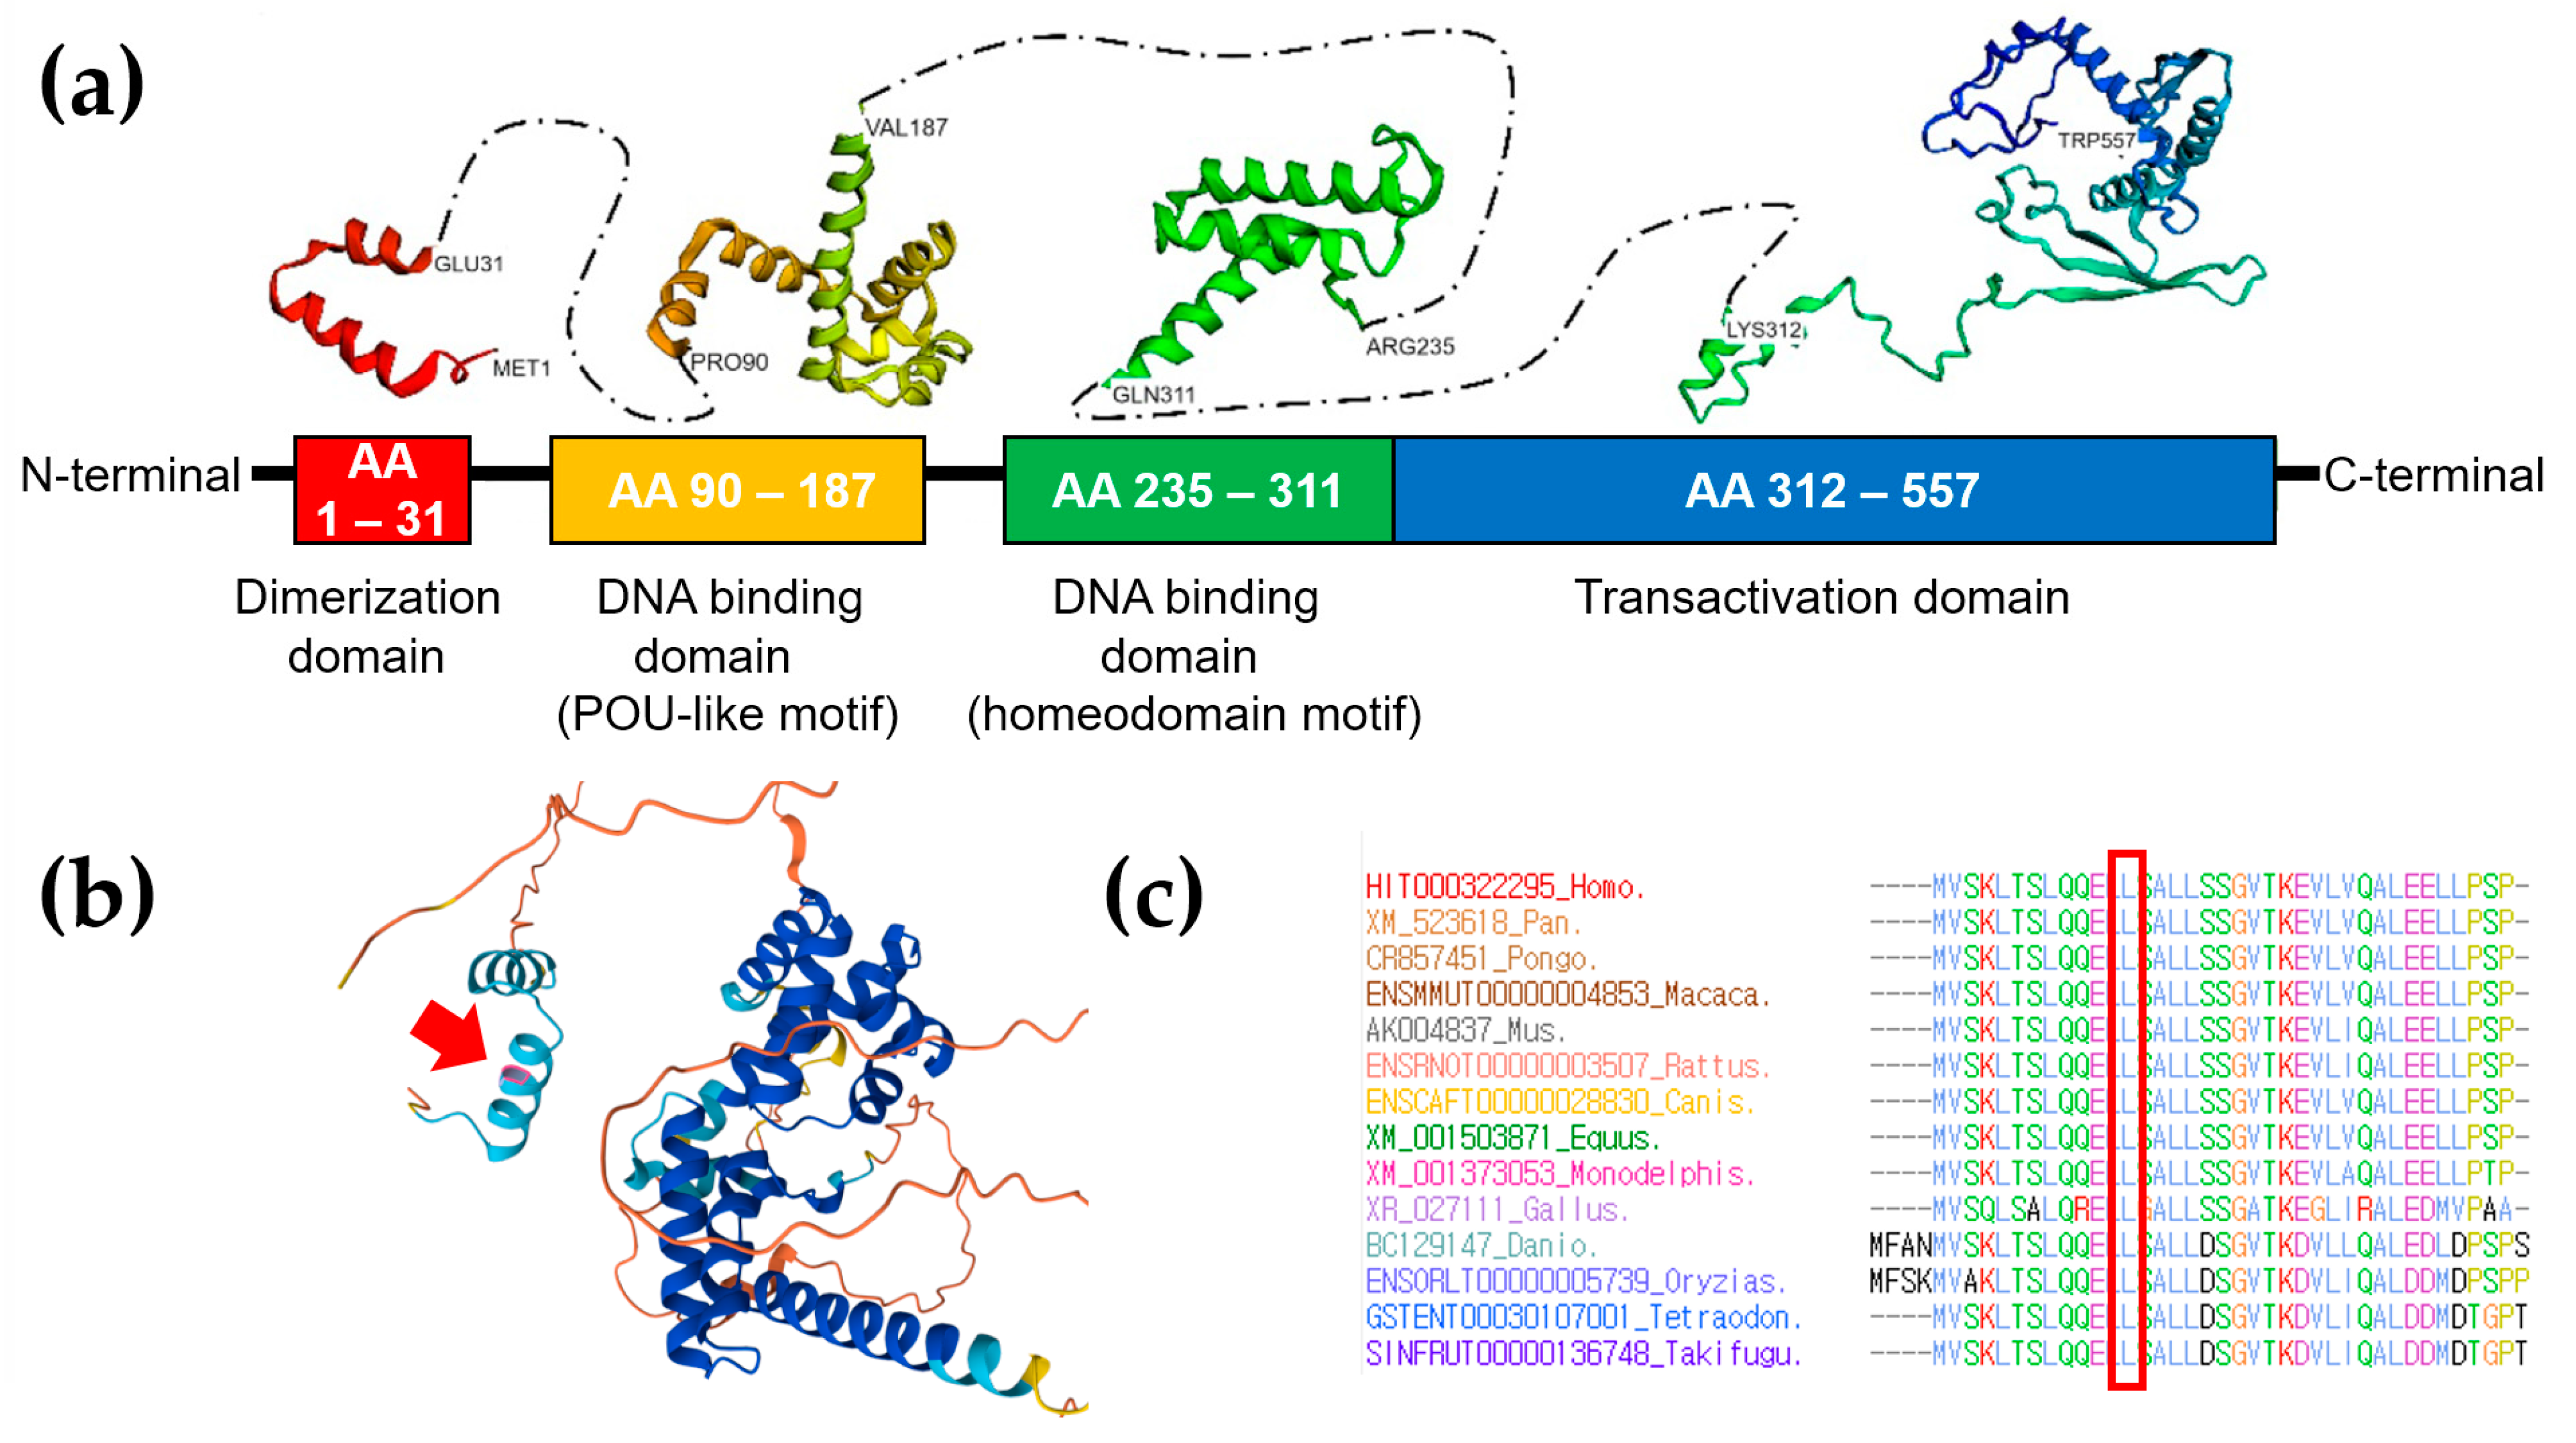

3. Genetic Testing

4. Discussion